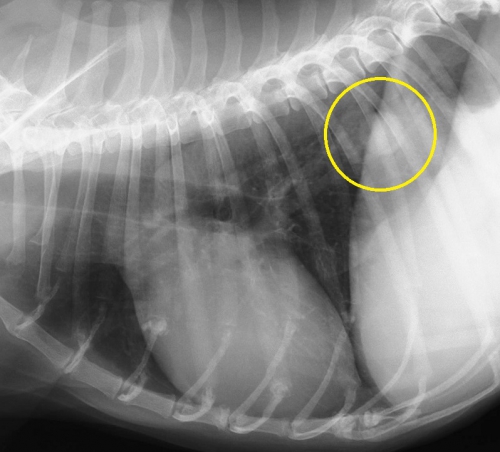

下2枚の写真は同じ犬の胸部レントゲン写真です。どちらも黄色の丸の中に白い円形の何かが見えると思います。

実はこの写真は肺転移した腫瘍のパターンなのですが、上のCRより下のDRの画像の方がよりはっきりと異常を確認できます。どちらも同じデジタルレントゲンなのですが、異常を際立たせるという意味でもDRに優位性があります。